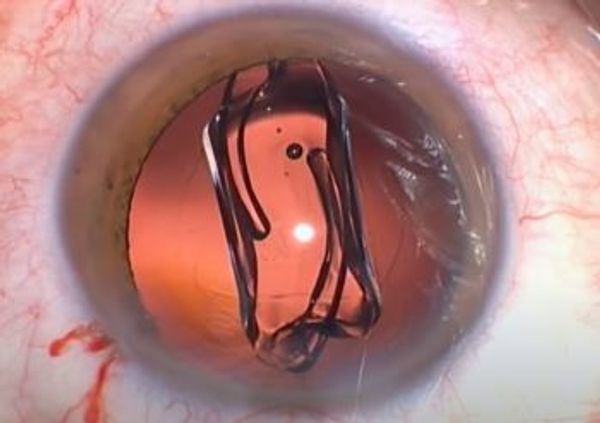

Der Graue Star kann nur durch eine Operation behoben werden; es gibt keine Medikamente, die die Symptome lindern können. Bei der Operation wird die trübe Linse durch eine maßgefertigte Kunststofflinse mit der richtigen Stärke ersetzt. Dazu wird unter lokaler Betäubung mit Augentropfen ein kleiner Schnitt von zwei bis drei Millimetern in das Auge gesetzt. Dabei wird die trübe Linse zunächst zerkleinert und dann abgesaugt. Durch denselben Schnitt wird dann eine faltbare Kunstlinse in das Auge eingesetzt. Diese Linse entfaltet sich von selbst und haftet auch von selbst. Der kleine Einschnitt im Auge heilt leicht ab. Ein Augenarzt, der eine Kataraktoperation durchführt, wird niemals zwei Augen gleichzeitig operieren, um Sehstörungen zu vermeiden.